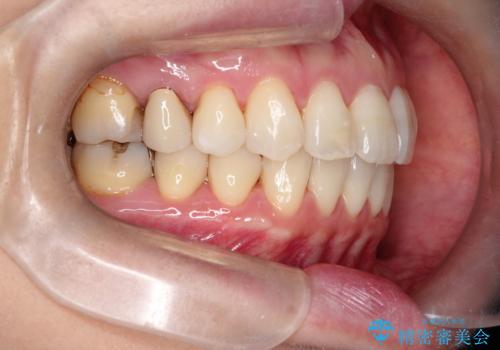

【インビザライン 】前歯を下げたい

- 前歯の凸凹と、前突を主訴に来院されました。

インビザライン にて治療を行なっております。

治療期間中はゴムかけを行なってもらうことで、前歯を下げることができました。